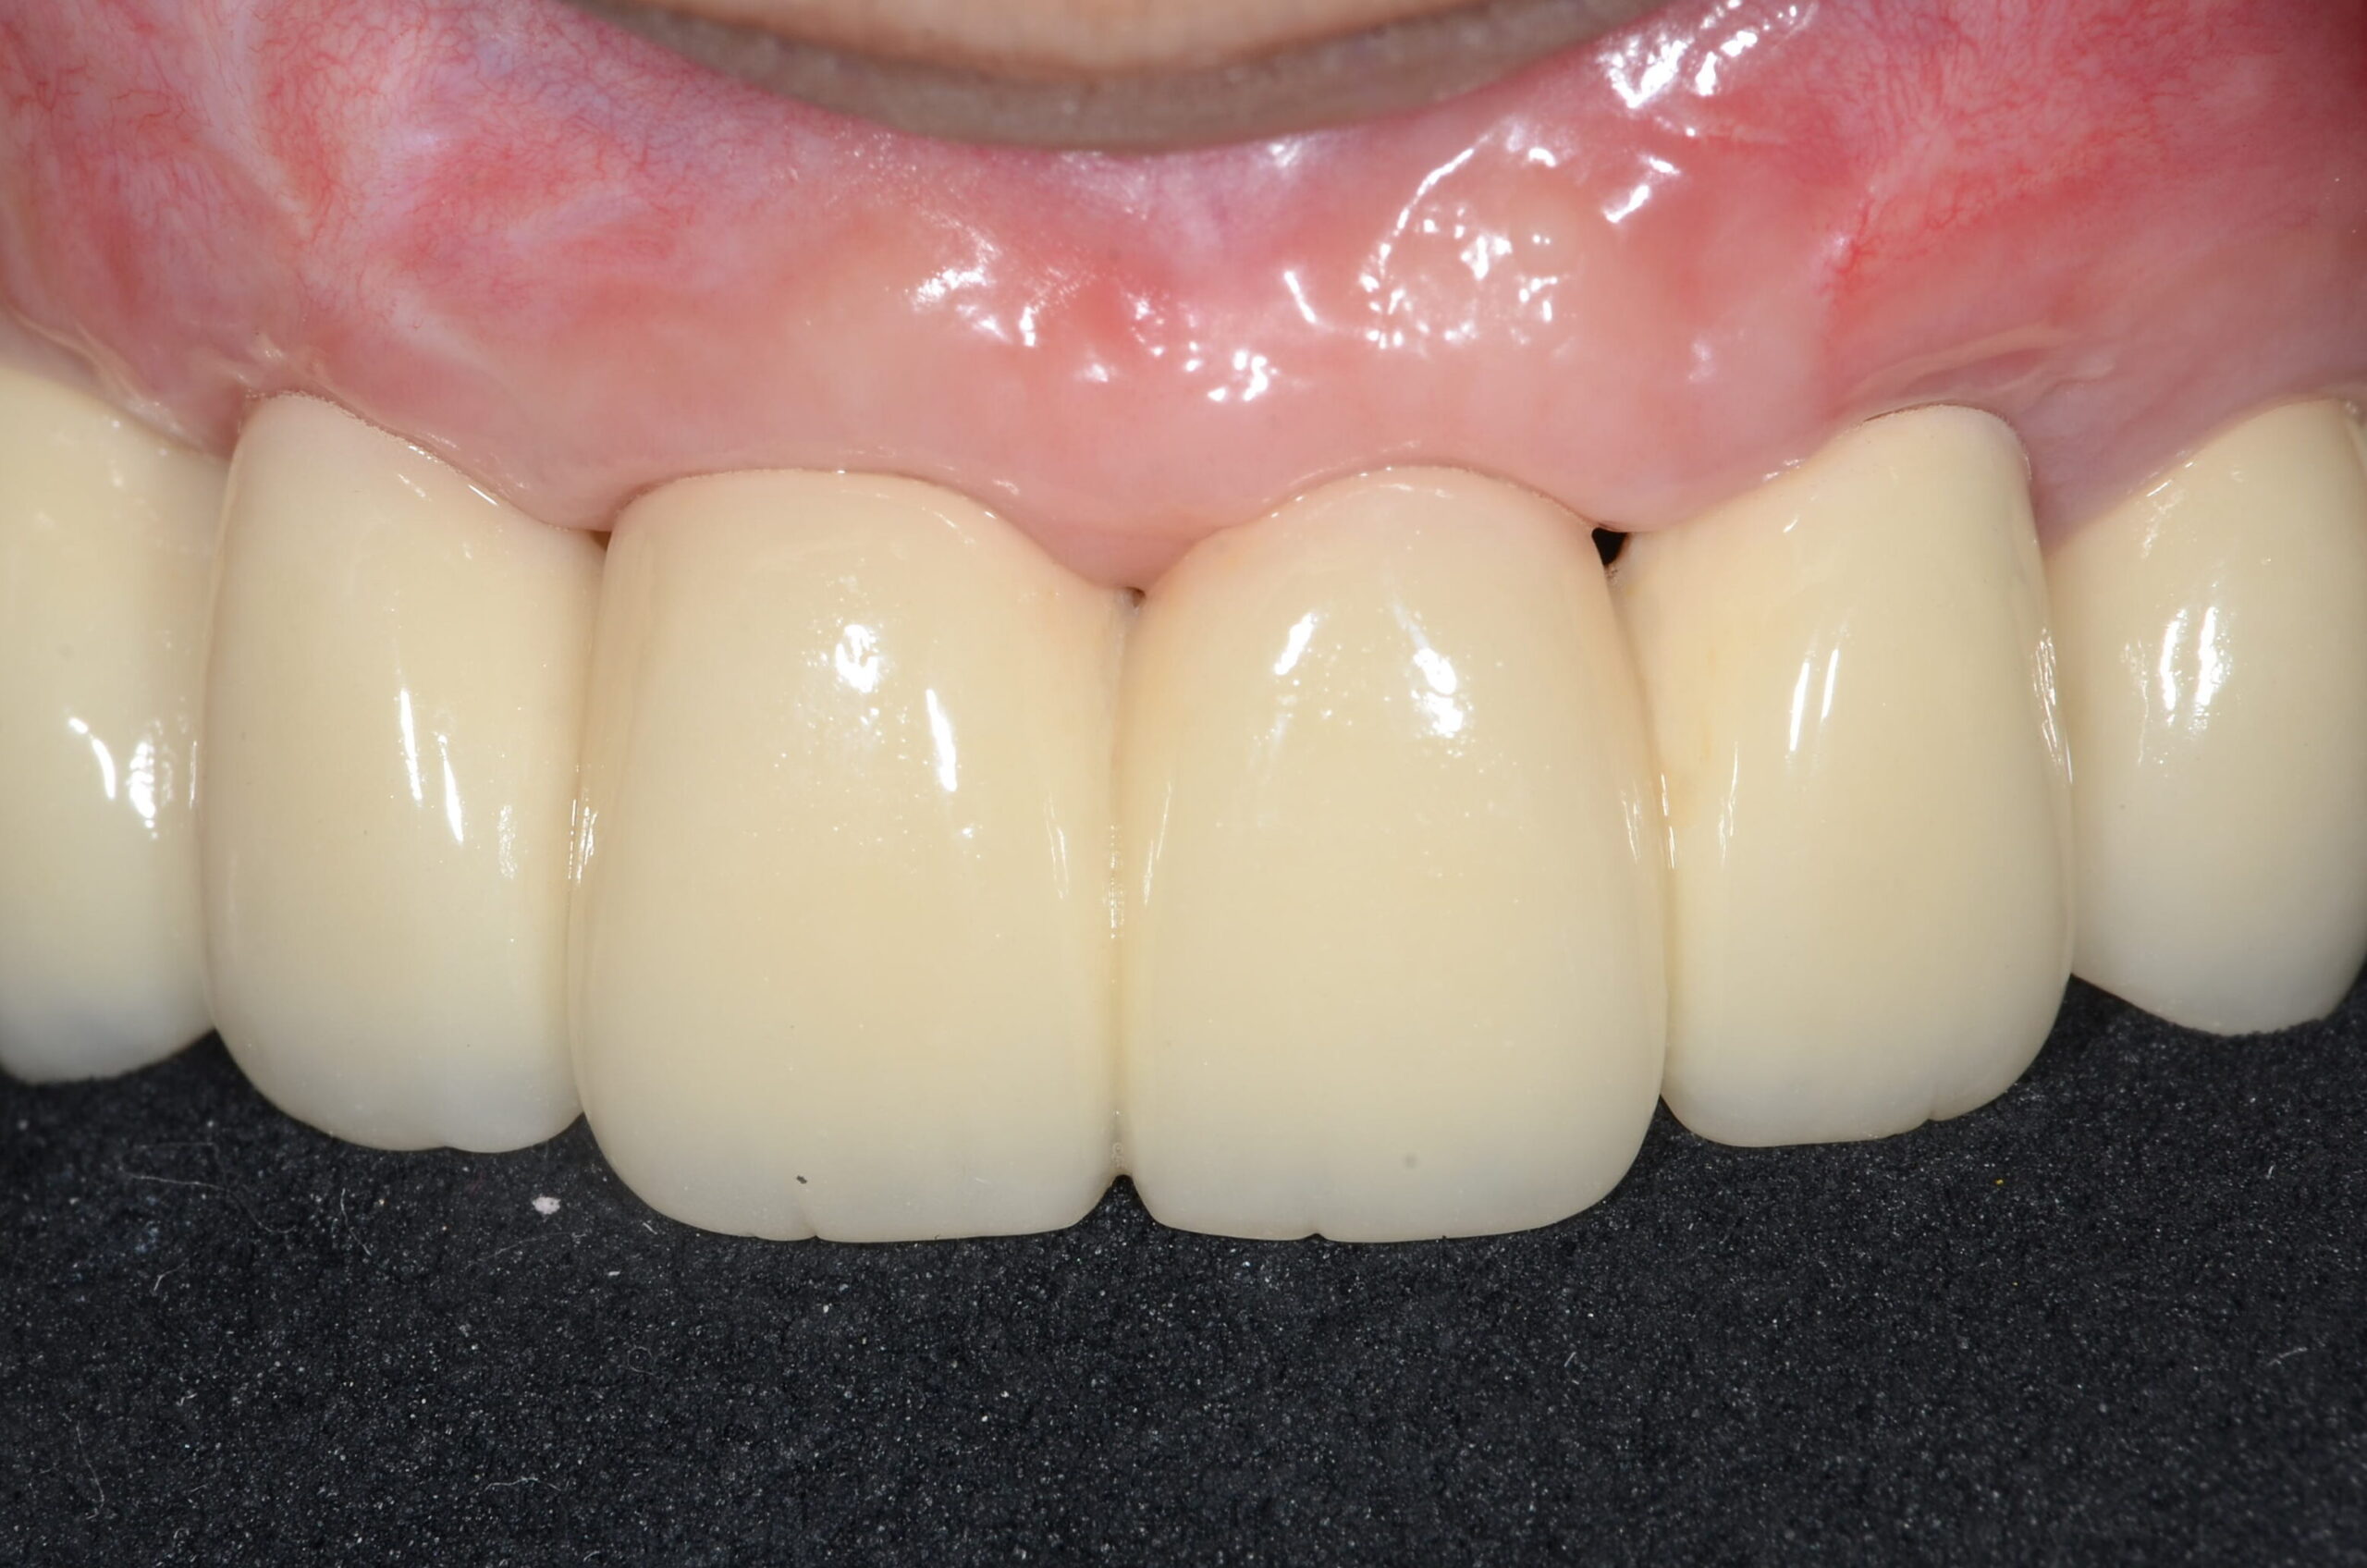

治療④ 上の前歯の被せ物

実際にお口の中にSETした写真になります